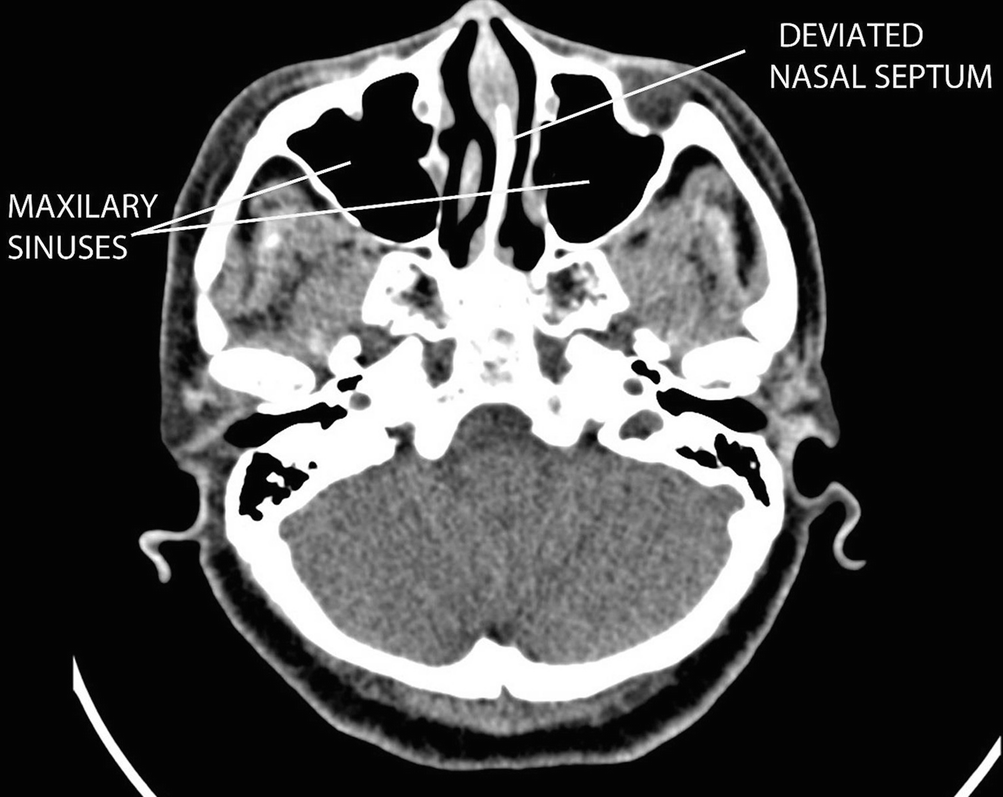

Fig. 12.7

CT PNS showing mucosal contact points in the nose

Rhinogenic headache is a headache or facial pain syndrome due to mucosal contact points in the nasal or sinus cavities in the absence of inflammatory sinonasal condition, purulent discharge, sinonasal polyps and mass or hyperplastic mucosa [2]. Neuropeptides and substance P are involved in the mediation of facial pain due to the contact between the mucosal surfaces [3]. The release of those mediators is responsible for the migraine-like headache symptoms. The treatment for rhinogenic headache is to remove or to release the contact points of the mucosal area in the nose (Fig. 12.7). This can be done via an endoscopic septoplasty and an endoscopic inferior turbinate reduction surgery (endoscopic turbinoplasty).